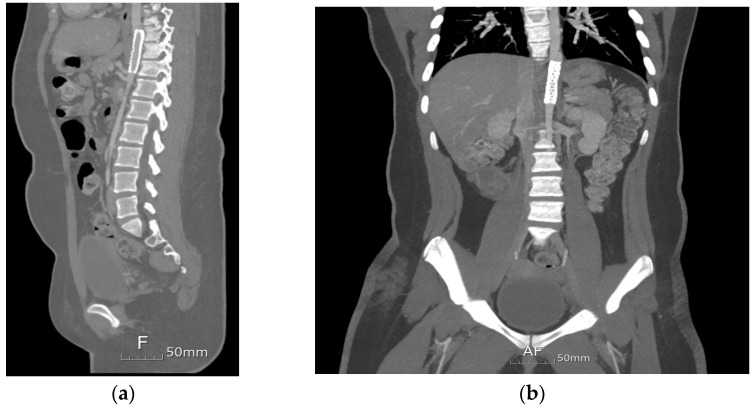

没有记录的病例导管引起的主动脉夹层的儿童患者。我们报告一个独特的情况下,儿童患者唐氏综合症谁开发了一个长期夹层主动脉瘤。患者在难以取出栓塞的动脉导管未闭装置10年后成功植入支架。唐氏综合症表现出复杂的临床情况,由于缺乏合作和不确定何时发生解剖,使得诊断具有挑战性,因为没有报告疼痛等症状。虽然在儿童中很少见,但重要的是要认识到经皮动脉导管未闭闭合后取出装置等手术是儿童主动脉夹层的潜在危险因素。

There are no recorded cases of catheter-induced aortic dissection in pediatric patients. We report a unique case of a pediatric patient with Down syndrome who developed a long-standing dissecting aortic aneurysm. The patient underwent successful stent insertion 10 years after experiencing difficulty retrieving an embolized patent ductus arteriosus device. The Down syndrome presented a complex clinical scenario, making diagnosis challenging due to a lack of cooperation and uncertainty about when the dissection occurred, as symptoms like pain were not reported. Though rare in children, it is vital to recognize procedures such as percutaneous closure of patent ductus arteriosus followed by device retrieval as potential risk factors for aortic dissections in the pediatric population.